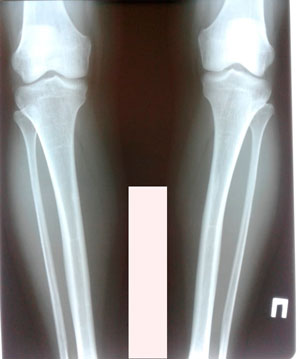

Дата операции - 11.07.2019г.

Дата снятия аппаратов - 08.10.2019г.

Срок сращения - 88 дней.